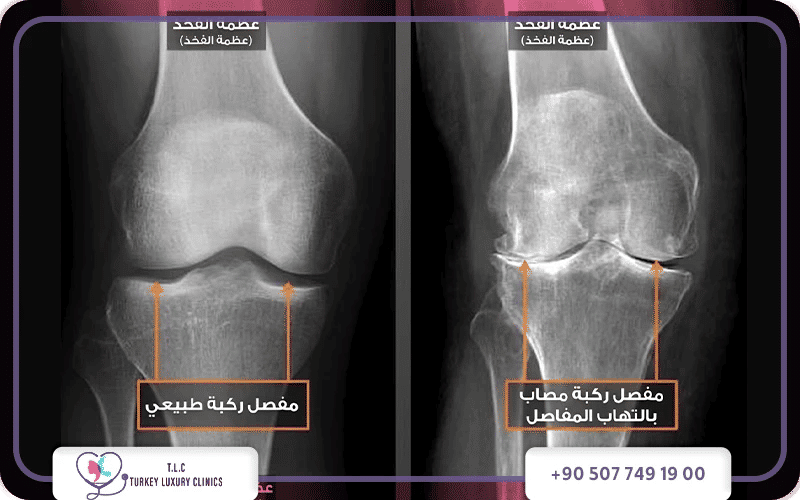

يظهر شكل خشونة الركبة بالصور على هيئة ضيق المسافة بين عظام المفصل، وتكون نتوءات عظمية، وتقوس في الساقين في الحالات المتقدمة. تبدو الركبة المصابة بتورم، واحمرار، وأحياناً اعوجاج ظاهر عند المشي.

يبدو شكل خشونة الركبة بالصور على هيئة تضيق في المسافة بين عظام مفصل الركبة نتيجة تآكل الغضروف الذي يغطي أطراف العظام، يعمل هذا الغضروف كوسادة مرنة تمتص الصدمات وتمنع احتكاك العظام ببعضها، ومع تآكله التدريجي تبدأ التغيرات بالظهور جلياً في صور الأشعة.

توضح صور الأشعة السينية شكل خشونة الركبة بالصور بشكل دقيق، حيث يمكن ملاحظة تضيق المسافة المفصلية بين عظم الفخذ وعظم الساق، كما قد تظهر زوائد أو نتوءات عظمية حول حواف مفصل الركبة، وتساعد هذه العلامات الأطباء على تقييم شدة الخشونة وتشخيص الحالة.

هنا تظهر أهمية تصوير الركبة بالأشعة السينية! والتي من خلالها يقيم الطبيب التغيرات داخل المفصل مثل تضيق المسافة بين العظام وظهور النتوءات العظمية، وهي العلامات التي تساعد على تحديد درجة الخشونة بدقة.

تظهر الأشعة السينية (X-ray) حالة العظام ودرجة تأكل الغضاريف عبر مراقبة ضيق المسافة بينها، وتُجرى عادةً في وضعية الوقوف لتقييم ضغط الوزن على المفصل، بينما يصور الرنين المغناطيسي (MRI) تفاصيل الأنسجة الرخوة، الغضاريف، والأربطة بدقة عالية جداً.

فحص شكل خشونة الركبة بالأشعة السينية (X-ray)

عند فحص الركبة بالأشعة السينية، يستطيع الطبيب ملاحظة التغيرات العظمية المرتبطة بخشونة الركبة بدقة، ومن أهم العلامات التي تظهر في شكل خشونة الركبة بالصور الإشعاعية:

- تضيق المسافة المفصلية الواضح بين عظم الفخذ وعظم الساق.

- ظهور النتوءات والزوائد العظمية حول حواف المفصل نتيجة الاحتكاك.

- زيادة كثافة العظم أسفل الغضروف، خاصة في المراحل المتقدمة من المرض.

بشكل عام، تعتبر الأشعة السينية هي الخطوة الأولى والأساسية لتشخيص وتقدير درجات خشونة الركبة بالصور، بينما يتدخل الرنين المغناطيسي لتقديم تقييمٍ أكثر عمقاً عندما تكون الأعراض غير واضحة أو عند الاشتباه بوجود إصابات أربطة إضافية.